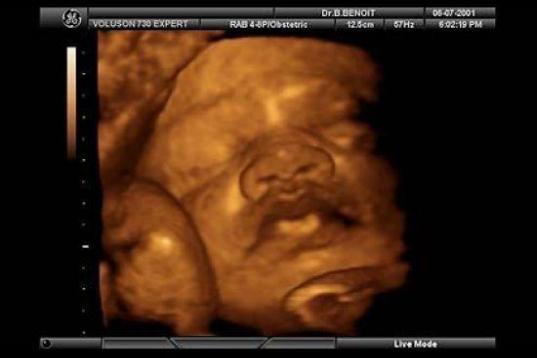

En esta galería puedes ver en fotos como es el desarrollo de un feto de semana en semana:

Desarrollo del feto, en fotos